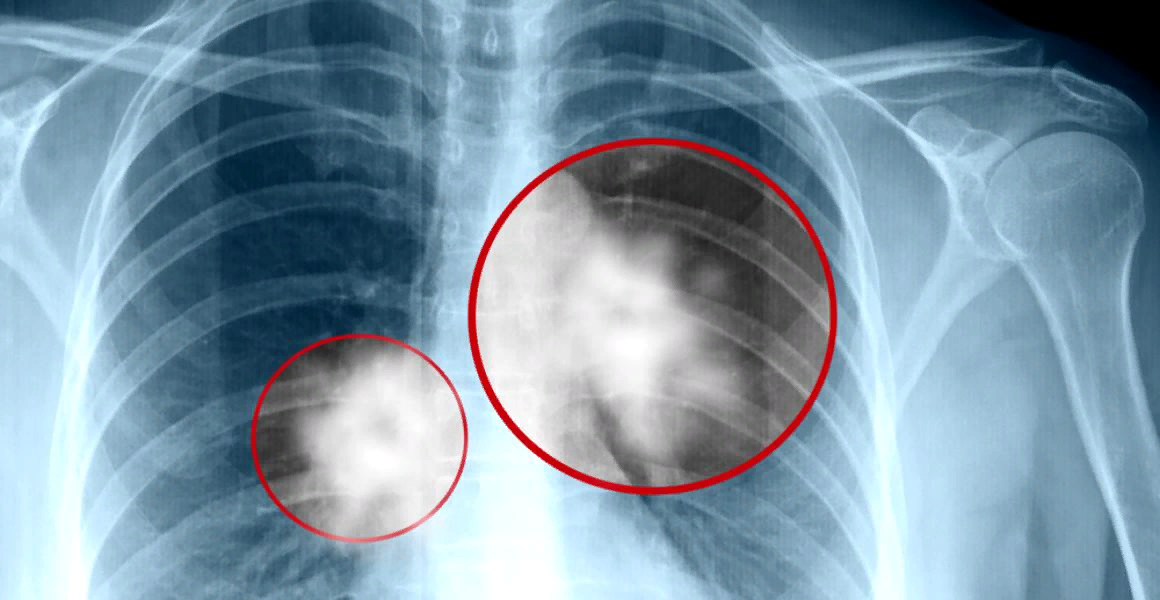

5 признаков рака лёгких, о которых нужно знать

Но смертность этого заболевания с каждым годом идет на спад, благодаря раннему обнаружению болезни. Именно поэтому мы составили список из 5 признаков рака легких.